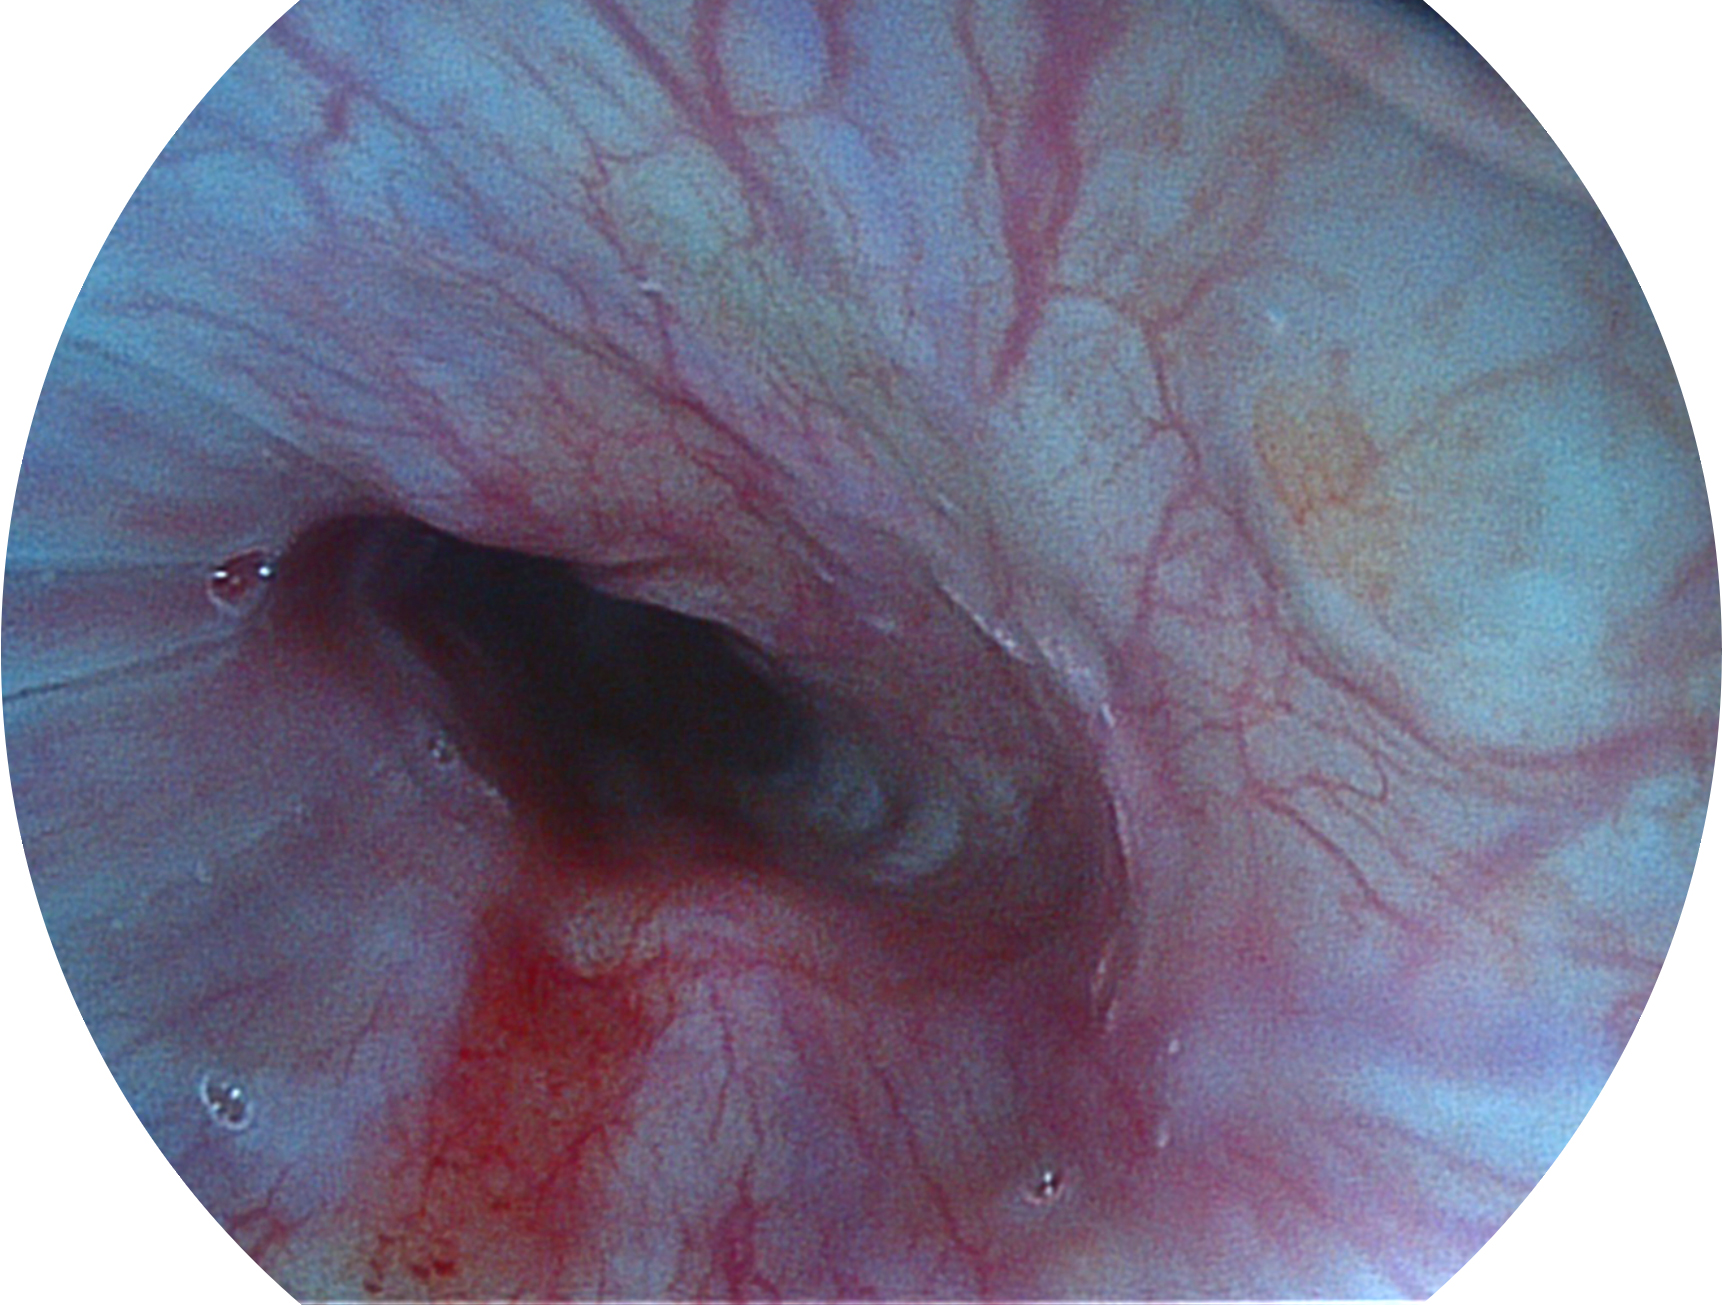

1xBET新开发的内镜染色技术,主要是基于多波长LED 光源的开发,VLS-55Q 四波长LED 光源是由四个不同颜色的LED光按照相应照明模式所规定的特定发光比例进行合束后形成,合束后形成的照明光的光谱由红光、绿光、蓝光及蓝紫光这四个不同的波段范围构成。具有更高光谱自由度,通过光谱比例的控制,实现了聚谱成像技术,英文全称为“Spectral Focused Imaging, SFI”,缩写为“SFI”和光电复合染色成像技术,英文全称为“Versatile Intelligent Staining Technology, VIST”,缩写为“VIST”。